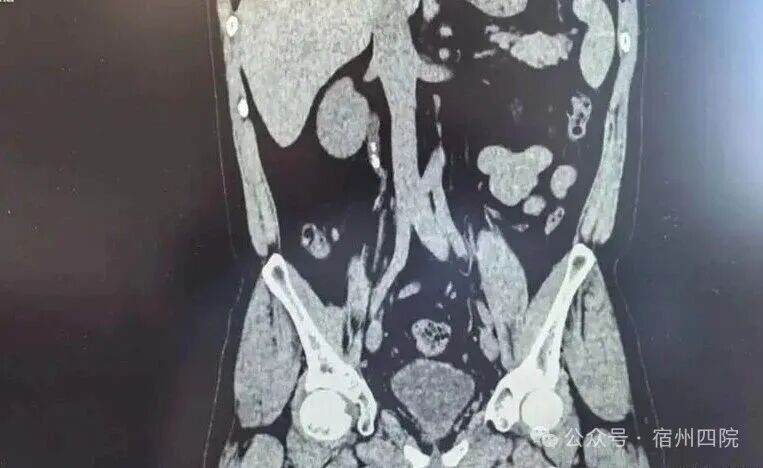

患者徐某,因结石症状未完全缓解,辗转至我院复查,门诊彩超提示右输尿管上段结石伴肾积水。面对这一情况,泌尿外科团队迅速评估,完善术前检查,排除手术禁忌症后,为患者实施了右侧经尿道输尿管软镜钬激光碎石术。术后次日复查无残石,患者顺利出院,对医院的诊疗技术、服务态度及设备先进性给予了高度评价。

输尿管结石是泌尿系统常见病,若未及时处理,可能引发肾积水甚至肾功能损伤。体外冲击波碎石(ESWL)是传统治疗方式之一,但部分患者因结石位置、大小或个体差异,术后可能出现排石不畅、残石等问题。如有患者经多次体外碎石后结石仍滞留输尿管,需进一步微创手术干预。

本次手术的治疗方案,采用了输尿管软镜钬激光碎石术。这一技术通过尿道插入软镜,直接定位结石并使用钬激光精准碎石,无需开刀,创伤小、出血少、恢复快,术后即可正常活动。尤其适用于复杂或难排结石,能有效避免结石残留及二次梗阻风险。